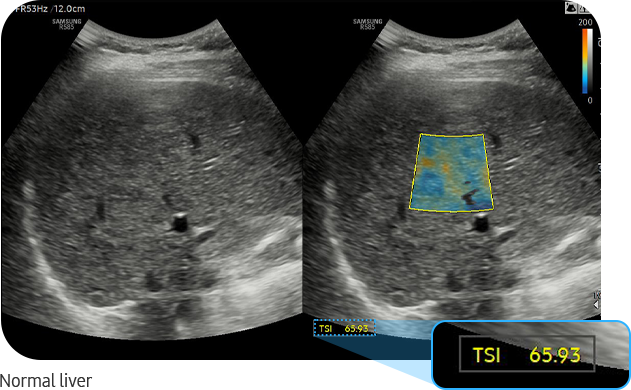

TSI™ (Tissue Scatter Distribution Imaging) is a tool that quantifies the scattered signal distribution based on backscattered signals. Scattering, the reflection of ultrasound waves in multiple directions not affected by their entry angle, produces speckle patterns in ultrasound images and this changes the distribution of backscattered ultrasound signals based on the scattering intensity.